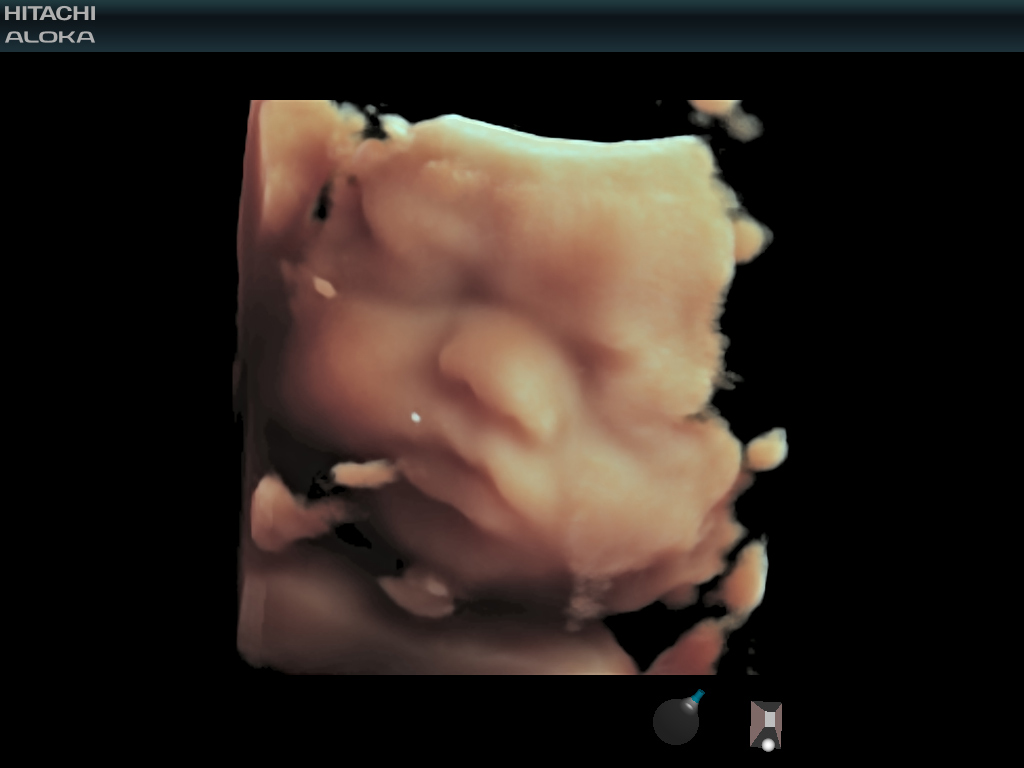

4D 자동 클리퍼는 최적의 절단면을 자동으로 정의하여 태아 앞의 태반 또는 기타 원치 않는 조직 신호를보다 쉽게 제거하여 표면이 렌더 된 태아 이미지를 명확하게 제공합니다.